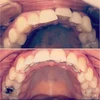

Diş Çapraşıklığı